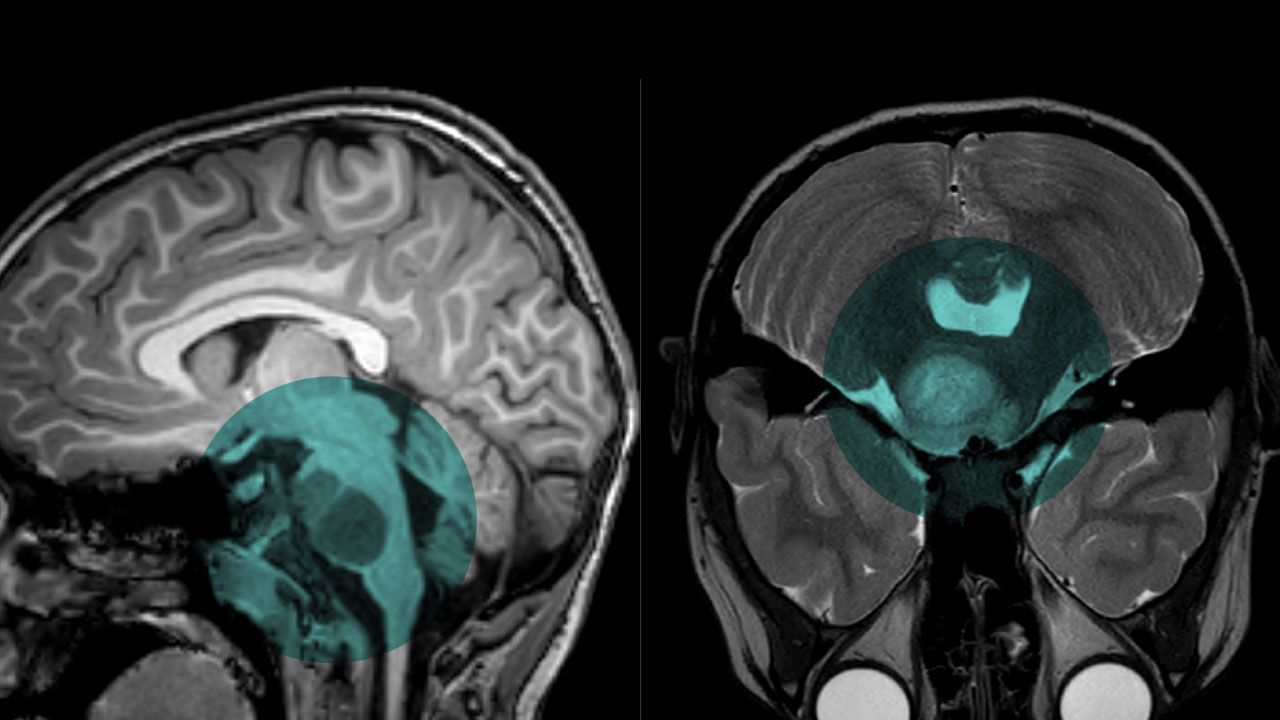

Um adolescente belga de 13 anos entrou para a história da medicina em 2024 ao se tornar o primeiro paciente do mundo considerado curado de um dos cânceres infantis mais agressivos já registrados: o glioma pontino intrínseco difuso (DIPG). O caso é tratado por especialistas como um marco científico no combate a tumores cerebrais pediátricos.

Lucas Jemeljanova foi diagnosticado aos 6 anos com o tumor, localizado no tronco cerebral — área vital responsável por funções como respiração e batimentos cardíacos. À época, os médicos informaram à família que ele provavelmente teria menos de um ano de vida.

O DIPG é raro, afeta principalmente crianças entre 4 e 6 anos e é considerado praticamente fatal. Menos de 10% dos pacientes sobrevivem por mais de dois anos após o diagnóstico. Até então, nunca havia sido registrada uma cura da doença.

O DIPG cresce rapidamente e atinge áreas extremamente delicadas do cérebro, o que dificulta cirurgias. Tratamentos convencionais, como quimioterapia e radioterapia, historicamente apresentaram resultados limitados.